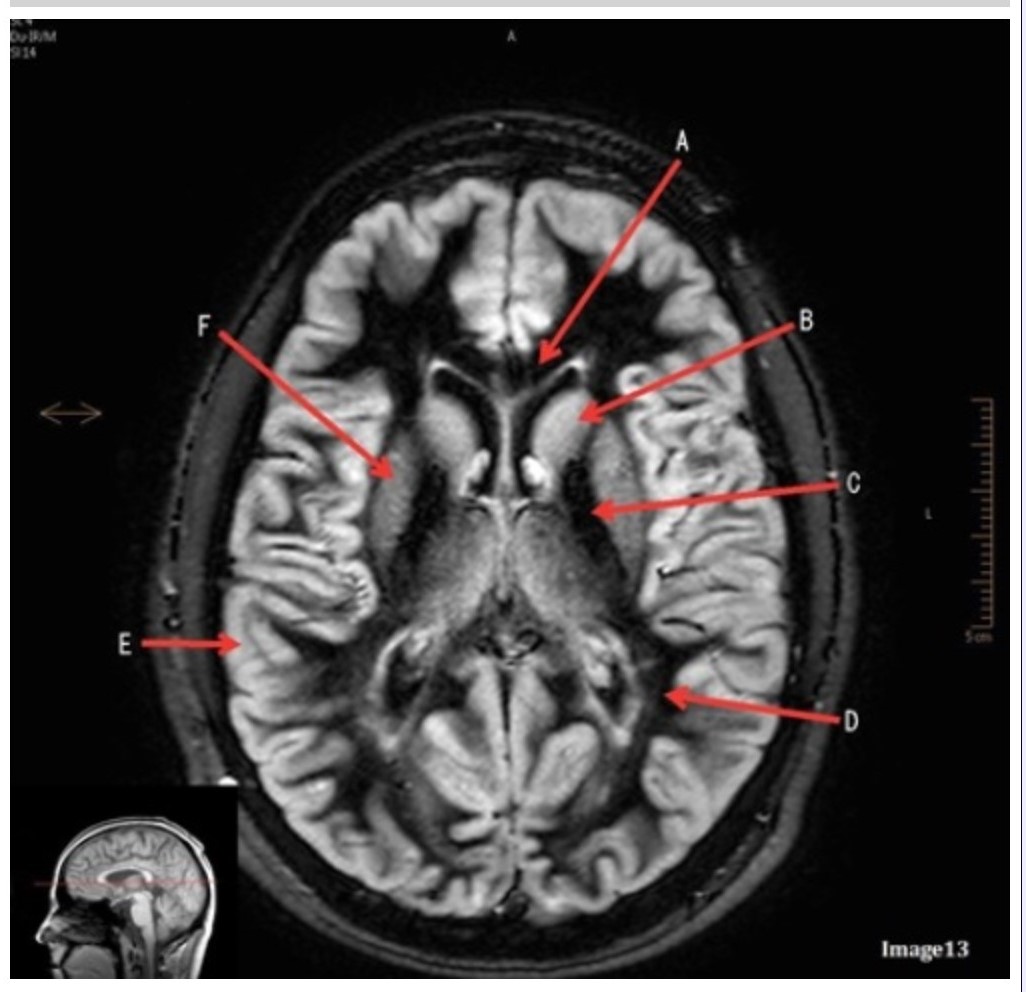

Letter E in Image 13 is pointing to:

A. Grey matter

B. White matter

C. Lentiform nucleus

D. Caudate nucleus

E. Internal capsule

Letter B in Image 13 is pointing to:

A. Splenium of the corpus callosum

B. Genu of the corpus callosum

C. Lentiform nucleus

D. Caudate nucleus

E. Internal capsule

Letter F in Image 13 is pointing to:

A. Grey matter

B. White matter

C. Lentiform nucleus

D. Caudate nucleus

E. Internal capsule

Letter D in Image 13 is pointing to:

A. Grey matter

B. White matter

C. Lentiform nucleus

D. Caudate nucleus

E. Internal capsule

Letter C in Image 13 is pointing to:

A. Splenium of the corpus callosum

B. Genu of the corpus callosum

C. Lentiform nucleus

D. Caudate nucleus

E. Internal capsule